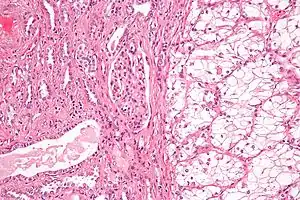

Carcinoma de células renais (CCR) é o cancro do rim com origem no revestimento do túbulo contorcido proximal, parte do sistema de canais muito finos do rim que transportam a urina primária. O CCR é o tipo mais comum de cancro do rim em adultos, sendo o responsável por cerca de 90–95% de todos os casos.[1]